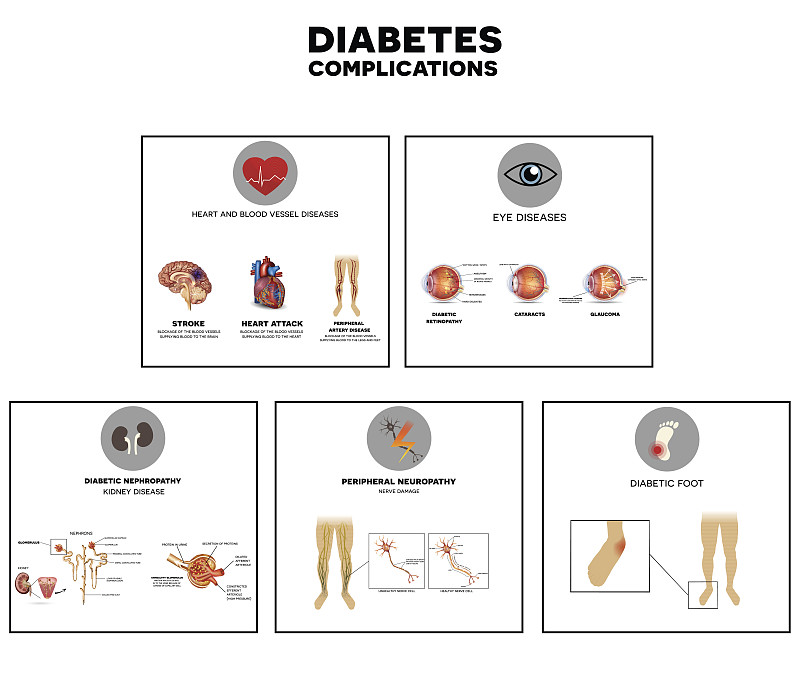

糖尿病并发症详情

糖尿病并发症信息图表详情